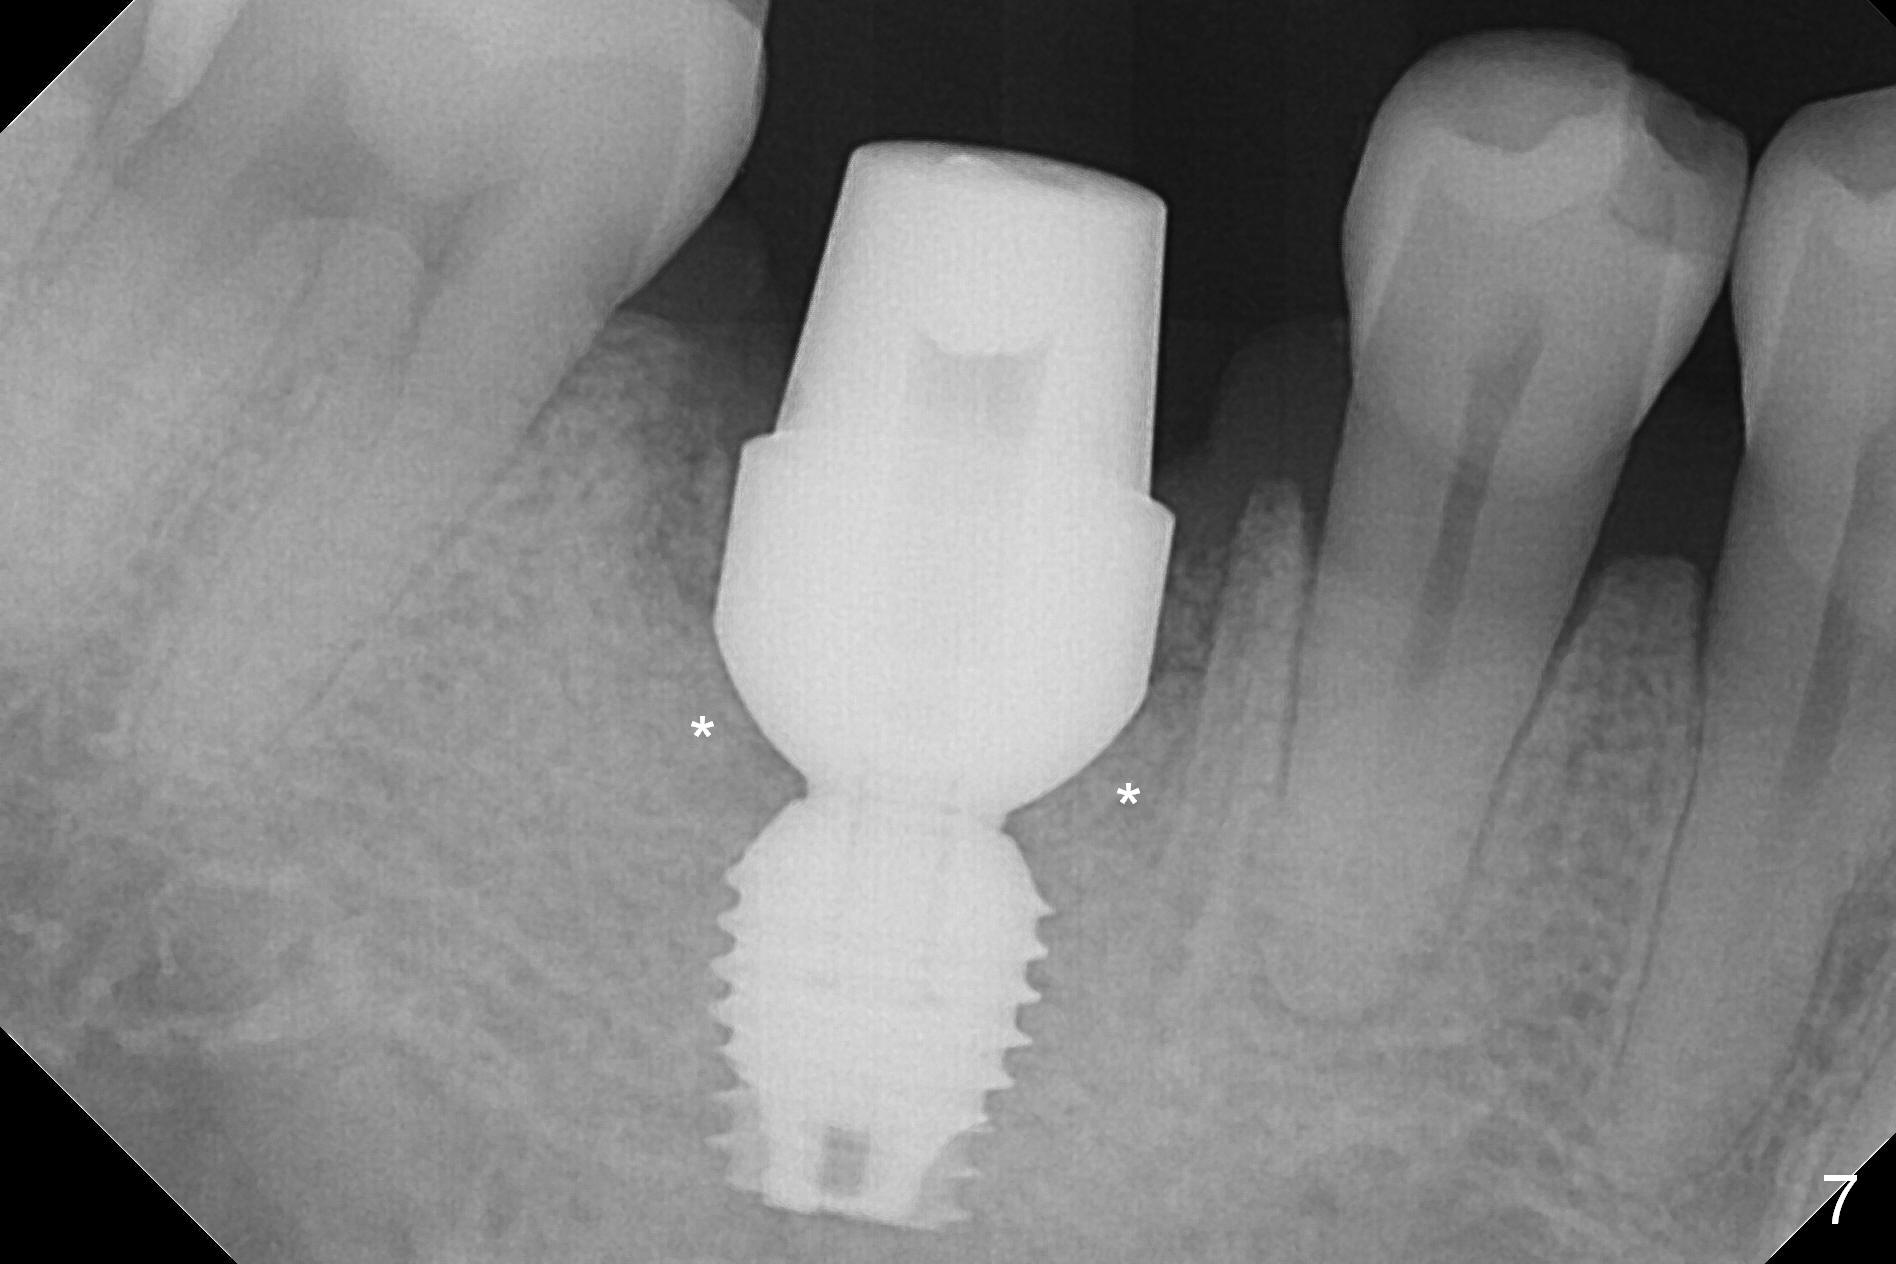

After extraction of the tooth #30 with Class V furcation involvement (Fig.1 (>),2 (L: lingual)), initial osteotomy depth is 8 mm with infiltration anesthesia, but a parallel pin is able to be inserted for 16 mm without pain (Fig.3). There is oozing from the osteotomy. Osteotomy increases in diameter with depth at 8 mm (Fig.4 (3.8 mm drill),5 (5.3 mm tap)). As the Inferior Alveolar Canal (IAC) is indistinct with increased pain during osteotomy, a 5.9x6 mm implant is placed with >50 Ncm following Septocaine infiltration (Fig.6). When bone graft (Fig.7 *) and 7.8x5.5(6) mm abutment (Fig.7,8) are placed, panoramic X-ray is taken (Fig.9). There appears to be a thick layer of spongy bone in the posterior mandible between the red and yellow dashed lines (Fig.5,9). Panoramic X-ray and/or CBCT should be taken if preop PA does not reveal IAC. This patient seems to be a bruxer. There are mandibular tori. Bone loss (furcation involvement) is not proportional to his oral hygiene status. Functional loading (progressive) should be delayed due to bruxism and the short implant.